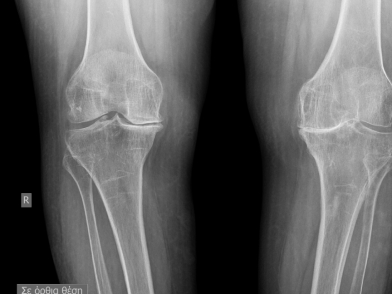

Οι απλές ακτινογραφίες του γόνατος, ιδίως με φόρτιση της άρθρωσης, είναι τόσο χαρακτηριστικες ώστε να καθιστούν άχρηστες πιο ειδικές εξετάσεις. Η ασσύμετρη στένωση του μεσαρθρίου διαστήματος, η σκλήρυνση του υποχόνδριου οστού, τα οστεόφυτα στα όρια της άρθρωσης καθώς και ευρήματα προηγουμένων παθήσεων (κατάγματα , χονδρασβεστώσεις κλπ) είναι ευρήματα οστεοαρθρίτιδας του γόνατος.